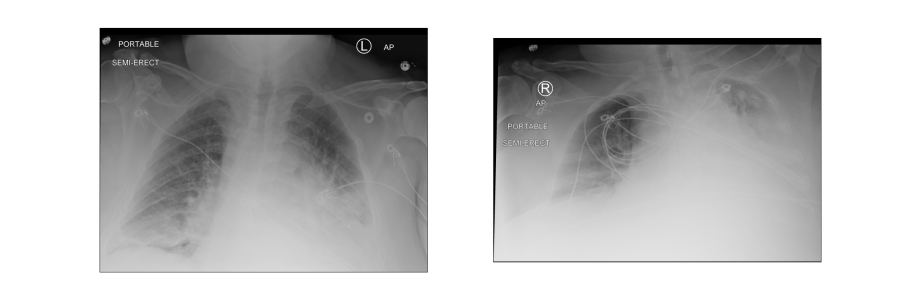

Figure 3 illustrates the frameworks for each of the prediction tasks over the succeeding 24 hours. Figure 3(a) shows an example of SIP predictions from a patient with increased lung opacity. In this case the patient did not suffer any adverse event in the next 24 hours, but ultimately suffered all three adverse events within 72 hours. Figure 3(b) shows an example of ORP predictions from a patient that required increased oxygeen within 24 hours. In Figure 3(c), a sequence of chest X-rays with increasing lung opacity is used by the MIP model to predict COVID deterioration for a patient. The images were taken 49 hours apart. For the case of Figure 3(c), the patient was transferred to the ICU, intubated, and suffered a mortality within 24 hours.

Refer to caption MIP Predictions ICU24: 0.784 Int24: 0.782 Mor24: 0.965

(c)

Figure 3: Example model outputs for ICU (ICU24), intubation (Int24) mortality (Mor24), and oxygen greater than 6 L per day (>6L24) prediction tasks, all at 24 hours. (3(a)) Example SIP outputs based on a single image with evident increased lung opacity. In this case the patient did not suffer any adverse event in the next 24 hours, but would ultimately suffer all three adverse events within 72 hours. (3(b)) Example ORP output based on a single image. This patient required greater than 6 L per day of oxygen within 24 hours. (3(c)) Example MIP outputs. Both images were taken from the same patient with 49 hours of separation. Increased lung opacity is observable in the second (later) image. The patient suffered all three adverse events within 24 hours.